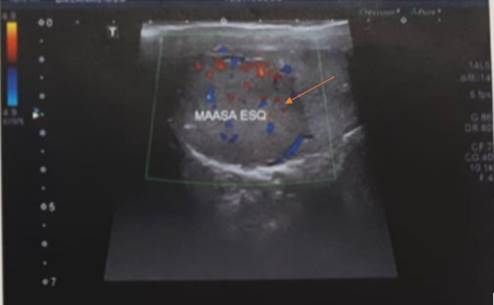

A 32-year-old male patient, white, without comorbidities or history of previous surgeries, who noticed a palpable solid nodule in the left testicle, without scrotal enlargement, looked for a urologist who performed color Doppler ultrasound of the testes, confirming the mass (Figure 1).